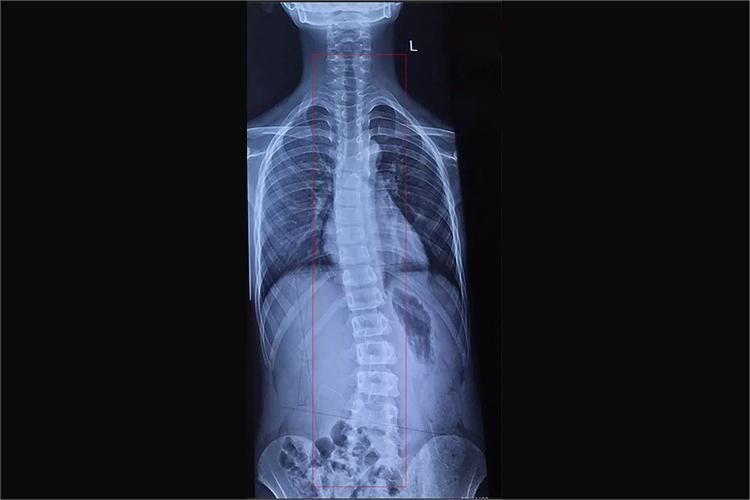

脊柱侧弯是指脊柱的一个或数个节段在冠状面上偏离身体中线向侧方弯曲,形成一个带有弧度的脊柱畸形,脊柱侧弯15度属于轻度。

脊柱侧弯15度属于轻度,凸侧椎弓根移向中线,但未超出第一格,凹侧椎弓根变小。此时侧弯的肋骨头不与椎体相重叠。其特点是男性多于女性,多为胸椎的左侧弯,常并发有其他畸形,最常见的斜头畸形,其次是智力低下,或先天性髋脱位。患者无明显身体不适,一般都是由体检拍片发现。